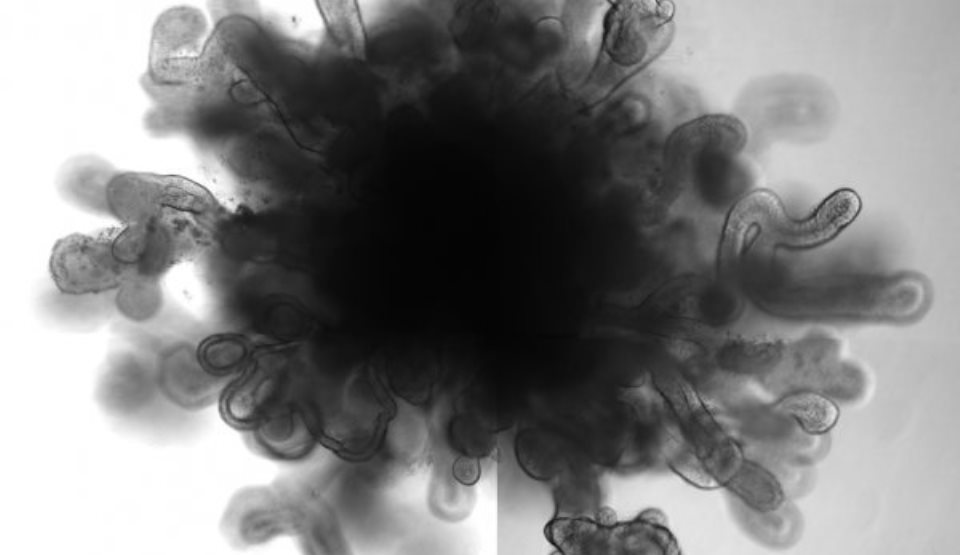

Cercetătorii din Centrul pentru Cancer al Universităţii din Colorado, SUA, au adunat date statistice din 108 cazuri de transplant şi au depistat că, la trei ani după tratament, pacienţii care au beneficiat de transplant cu celule stem din sângele ombilicoplacentar erau supuşi unui risc mult mai mic de complicaţii cronice.

Mai precis, rata de boală grefă-contra-gazdă a fost de cinci ori mai mică în cazul pacienţilor care au beneficiat de transplant cu celule stem din sângele ombilicoplacentar, faţă de cei cu transplant de celule stem din măduva osoasă (8% faţă de 44%).